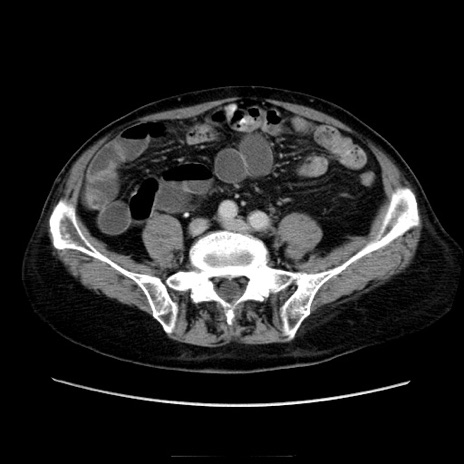

症例21(横断像)

【症例】70歳代男性

【主訴】腹痛

【現病歴】肝硬変・肝細胞癌にてかかりつけの方。約9時間前に食後より腹痛出現。症状が徐々に増悪し、嘔吐出現したため来院。

【既往歴】肝硬変、肝細胞癌(RFA、TACE後)

【身体所見】意識清明、表情苦悶様、BT 36℃、BP 129/78mmHg、P 88bpm、SpO2 97%(RA)、右上腹部から心窩部にかけて圧痛あり、反跳痛なし、筋性防御あり。

【データ】WBC 5800、CRP 0.16